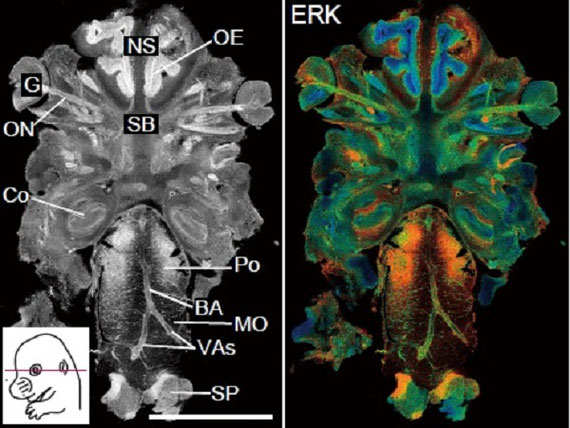

マウスの脳を見ると、分子の活性を色分けしてみることができます。

ヒトやマウスの組織から採った細胞を使って、細胞同士がどのようにコミュニケーションをとっているか、蛍光タンパク質を使ったツールと、高度な顕微鏡技術を用いて観察しています。

そこで、クラゲの蛍光タンパク質を材料に、細胞増殖因子の働きを顕微鏡で見えるようにする道具を開発しました。その結果、この細胞増殖因子は、隣の細胞へ信号を伝えるためにあり、バケツリレーのように遠くまで信号を伝えていることが判明しました。